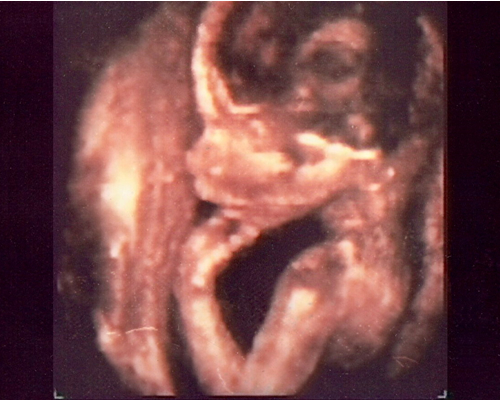

Pero la realidad científica revela que durante ocho meses y medio esa persona que está en el entorno peculiar del útero materno crece y en él se perfilan -casi sin que nadie lo sepa- los rasgos de lo que es y será también con canas, sólo dejando transcurrir unos años...

La investigación biomédica ha reformado en los últimos años el estudio de la vida fetal, donde se apoya la Perinatología. William Liley, investigador en Psicología Perinatal y en fetología, creador de las celebres "curvas de Liley" del líquido amniótico para controlar el grado de afectación del RH en el feto, afirma que hay que considerar el crecimiento de la persona con todos los datos, es decir, según el desarrollo celular y no sólo por los años que transcurren.

Cada ser comienza a existir a partir de una sóla célula y llega a alcanzar los 30 millones en la edad adulta mediante 45 sucesivas divisiones celulares. Poco antes de nacer, con 35 semanas aproximadamente de vida en el útero de la madre, ya se ha realizado 41 de estas divisiones y las 4 restantes tienen lugar durante la infancia y la adolescencia.

"Cuando teníamos una semana, anidamos en la pared nutritiva del útero de nuestra madre. A las dos semanas nuestro pequeño cuerpo enviaba unas señales químicas que fueron responsables del hecho de que a ella se le parara el ciclo menstrual. A las tre s semanas, nuestro corazone empezó ya a latir. A las seis semanas nuestro cerebro funcionaba ya, y fue entonces cuando comenzamos a movernos.

Al tiempo que nuestra madre perdía la segunda menstruación, nosotros eramos ya capaces de nadar libremente, con una brazada natural de nadador, en el saco fluido en el que nos encontramos; de agarrar un instrumento si alguien nos lo hubiera colocado en la palma de la mano y de que se nos hiciera un electrocardiograma.

En las salas de consulta de los ginecólogos existen los instrumentos que permiten a la madre oir el latido del corazón de su bebé de pocas semanas. En la décima semana, la estructura de nuestro cuerpo estaba completamente terminada. Aunque eramos tan pequeños que habríamos podido ponernos de pie sobre la uña del dedo meñique de nuestro padre, sin embargo nuestro cuerpo estaba tan desarrollado a los tres meses de vida, y cada uno de nosotros percibía el dolor, y se habría retirado de la punta de una aguja si la hubiera tocado. También nuestro oido funcionaba bien".

Samuel Alexander Armas es el feto más pequeño que ha sido operado hasta ahora mediante una novedosa técnica. Padecía de una anomalía llamada espina bífida, que tiene un orígen aún no determinado, pero que deja la columna vertebral abierta, lo que inevitablemente daña la médula espinal. Por lo general los niños quedan inválidos.

La nueva técnica permite sacar un feto del útero materno, operarlo, reinsertarlo e introducir el útero nuevamente en la madre.

El Dr. Joseph Bruner, médico cirujano estadounidense que realizó esta operación, nos plantea: "Una de los impactos de esta nueva técnica es que agrega una nueva perspectiva al tema del aborto. En mi país y creo que en casi todos los países, el feto no tiene derechos legales ni identidad, pero con esta nueva técnica quirúrgica estamos desafiando esos conceptos. ¡Si un médico puede diagnosticar y tratar un feto, eso lo convierte en un paciente! Y si el feto es un paciente, entonces, es una persona...Y las personas tienen derechos y privilegios y un status legal". A su juicio, la nueva técnica reabre un dilema para la sociedad.